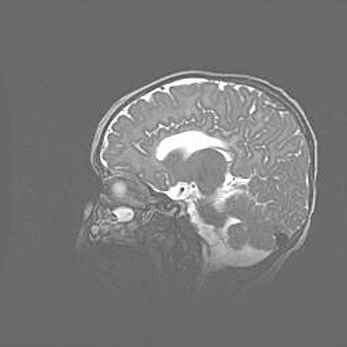

Подострая гематома правой гемисферы мозжечка.

Наружная гидроцефалия.

Возраст: 15 дней

Вес: 3100 г

Пол: женский

Окружность головы: 37 см

Срок гестации: 35-36 недель

При открытой наружной форме гидроцефалии у новорожденных расширяются и переполняются субарахноидные пространства.

Кровоизлияния в мозжечок имеют две клинико-анатомические формы: полушарные гематомы и кровоизлияния в червь.

К появлению этой патологии может привести: повреждения головного мозга, возникающие в результате асфиксии и гипоксии плода при беременности, или травмы во время родов. Редко гематома мозжечка может быть результатом первичной коагулопатии и сосудистой мальформации, диссеминированном внутрисосудистом свертывании, изоиммунной тромбоцитопении.